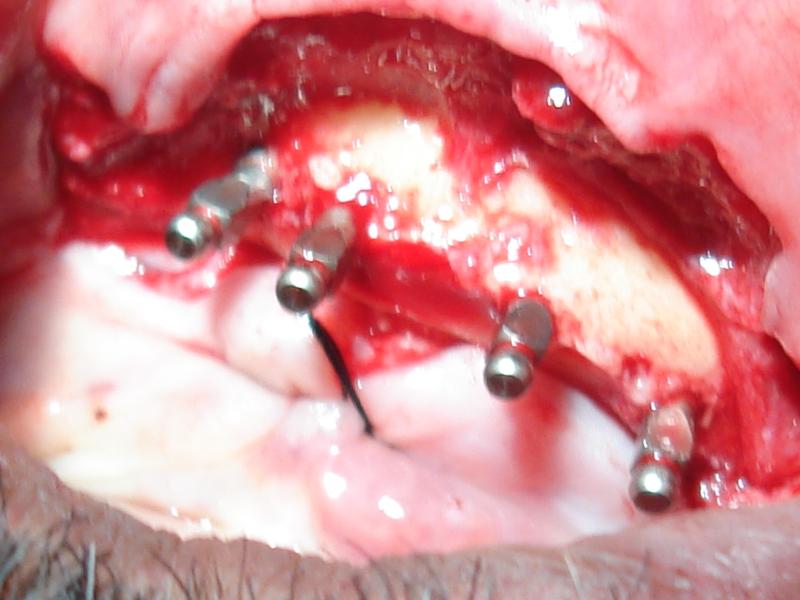

Surgical placement of implants